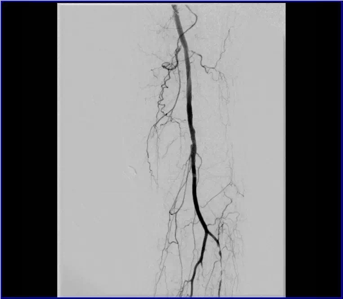

股動脈閉塞

動脈閉塞處支架植入